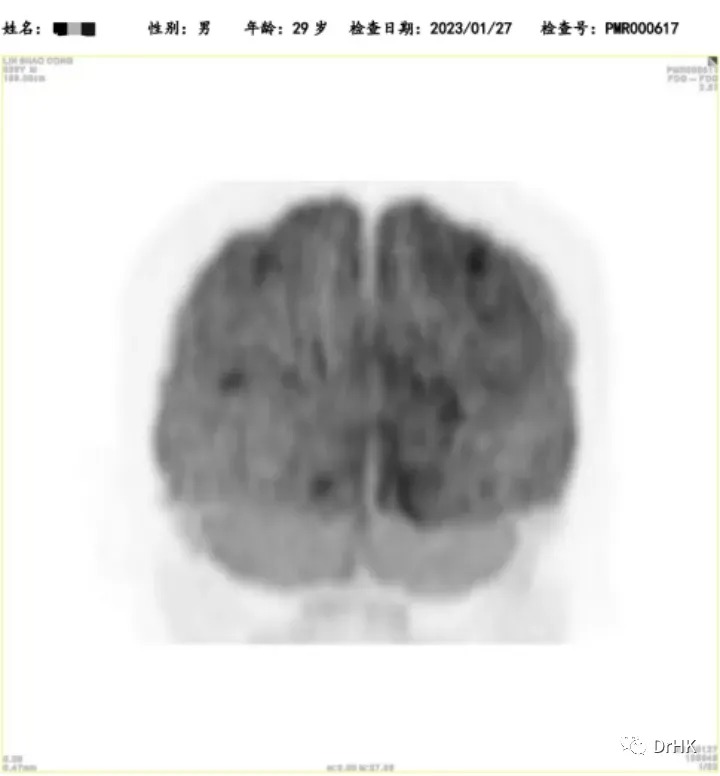

PET-CT

Deauville score: 5 points

Liver involvement: A lesion measuring approximately 3.2×2.6×3.7 cm, with a maximum SUV value of 22.4

Brain: Slightly low-density areas in the deep right temporal lobe and basal ganglia, suggesting lymphoma involvement based on MRI images

Multiple bone lesions: Bone absorption and destruction changes in multiple sites including the bilateral scapulae, clavicles, ribs, sternum, pelvic bones, and vertebrae. Some areas showed increased bone density, with the left iliac bone being the most prominent

Left gluteus maximus muscle: A lesion measuring approximately 1.2×1.6×1.5 cm, with a maximum SUV of 12.4

Starting from April 2, 2022, the patient was treated with the DA-TEDDi-R regimen combined with targeted therapy (ibrutinib + rituximab + dexamethasone + liposomal doxorubicin + etoposide + temozolomide + long-acting GCS + intrathecal Ara-C) for two cycles. After the treatment, the PET-CT assessment showed complete metabolic remission (the first complete remission since the onset of the disease), with a Deauville score of 2-3. Comparing this with the PET/CT imaging from our center on April 1, 2022, the liver lesion significantly decreased and the high metabolic activity disappeared; the left gluteus maximus lesion also disappeared. There were localized bone resorption and destructive changes in multiple bones (bilateral scapulae, clavicles, ribs, sternum, pelvic bones, and vertebrae), with some areas showing increased bone density, particularly in the left iliac bone. The bone marrow glucose metabolism was diffusely elevated, suggesting reactive changes post-treatment, and we recommended further evaluation with a bone marrow biopsy.

The patient was subsequently followed up regularly, with imaging evaluations completed six months and one year after the transplant. It is gratifying to report that the patient has maintained complete remission throughout this period. The PET images are shown below:

Six-Month Post-Transplant Imaging Evaluation